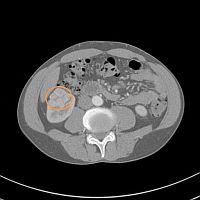

検査結果の画像を左欄に示します(マウスを重ねると拡大します)。

画像を見た結果は十中八九 癌であるということでしたが、なぜ十中八九なのかは説明はありませんでした。

さて慶應義塾大学病院でも2011年1月7日(金)に改めてCT検査を行い、2011年1月14日(金)に診察を受けました。 CT検査はやはり単純CTとヨード製剤を使用した造影CTです。 CTで計測された腫瘍の大きさは35mmでした。 さらに検査結果は以下のような観点で診断されます。

このようにして診断が下された私の検査結果は、ほぼ間違いなく癌であり病期分類は T1a N0 M0 のステージT期ということでした。